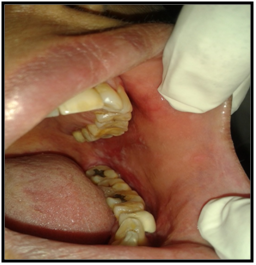

On intraoral examination, diffuse lesions in the form of erythematous areas were seen interspersed within white keratotic areas present all over the facial aspect of gingiva (Figure 2) and more posteriorly on the buccal mucosae bilaterally (Figure 3). Left buccal mucosa showed a white erythematous patch measuring approximately 2x2.5cms extending anteroposteriorly from the area adjacent to mandibular first molar to the retro molar pad area and superior inferiorly from the line of occlusion to the upper and lower lingual vestibule. White radiating striae (wickhamstriae) were present with an interspersed erythematous patch. Right buccal mucosa showed a more extensive lesion measuring approximately 2.5x3cms extending anteroposteriorly from the region adjacent to mandibular canine to the retromolar pad area and superioinferiorly from the upper gingiva buccal sulcus to the lower gingivobuccal sulcus and the alveolar mucosa. Borders of the lesion appear irregular and ill defined. On palpation, the lesions appeared to be tender. The surface of the lesions were rough and non scrapable with no induration noted.

Figure 3 The lesion on the facial gingiva.

Figure 2The Lesion on the Right and Left Buccal Mucosae.